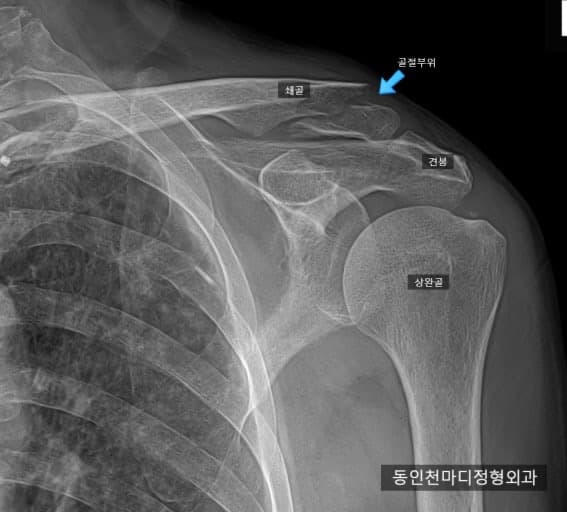

원위부 쇄골 골절 4주차에 팔걸이 풀어도 되나오?

지금 4주차인데 골전이 나오지도 않았는데 의사거 팔걸이를 무작정 풀자고 하는데 풀어도 되는건가요? 지금도 윰직이면 통증있고 심지어 3주차보다 더 틀어지고 벌어졌어요 저 사진은 제 사진은 아닌데 저런식으로 뼈가 밑으로 틀어졌는데 기능상 문제가 없는게 맞는건가요? 그리고 원위부 골절에는 팔자붕대는 효능이 없다는데 팔자붕대로 바꾸고 싶은데 안되는건가요?

• 1번 째 사진